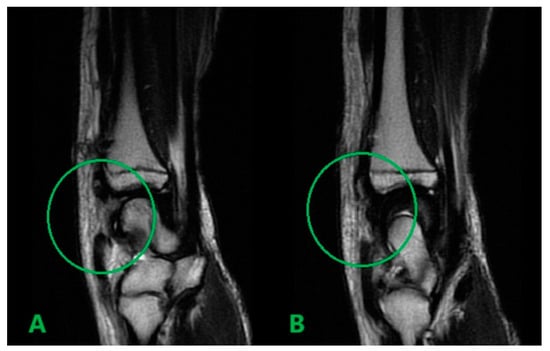

MRI scans showing the distal ends of the injured ECRL and ECRB tendons are shown in Figure 1. The extensor pollicis longus (EPL) tendon was preserved. After preparation, the patient underwent surgery. The procedure was performed under a tourniquet. The post-traumatic wound was widened proximally and distally to visualize and release scar tissue properly. After mobilization and resection of the tissue scar, the distal ends of the damaged radial extensors were visualized (Figure 2). The extent of the damage matched the MRI results. The proximal ends of the ECRL and ECRB formed a common scar and underwent retraction that did not allow mobilization (Figure 3).

Figure 1.

Preoperative sagittal T2 MRI scans showing the distal ends of the injured ECRL (A) and ECRB (B) tendons.